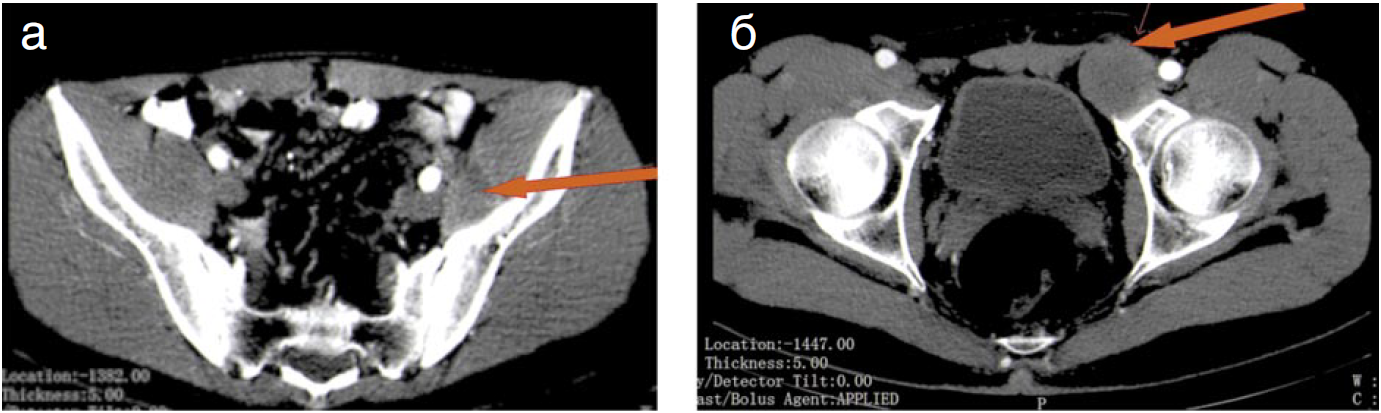

При КТ-ангиографии выявлено объемное образование в забрюшинном пространстве с четкими контурами размером 8,8×5,6×13 см, практически не накапливающее контрастный препарат (рис. 1). Опухоль оттесняет левую почку. По наружному контуру опухоли проходит левый мочеточник. По верхнему контуру образования проходят почечные сосуды. По задней поверхности опухоль инфильтрирует поясничную мышцу, тесно прилежит к брюшной аорте, левой общей подвздошной артерии, инфильтрирует наружную подвздошную артерию. Нисходящая ободочная кишка и сигмовидная кишка распластаны на опухоли. На уровне крыла левой подвздошной кости определяется аналогичное образование размером 4,3×3,9 см, протяженностью 7 см, которое пролабирует из брюшной полости в левую паховую область через левый паховый канал. По наружному контуру опухоли определяется стентированный левый мочеточник.

Рис. 1. Пациент C., 24 года. КТ. Аксиальные срезы. Артериальная фаза. Забрюшинно слева определяется практически аваскулярная опухоль с неровными, частично четкими контурами, инфильтрирующая левую поясничную мышцу (а), окружающая левую подвздошную артерию (б) – указано стрелками.

Fig. 1. Patient S., 24 years old. CT. Arterial phase axial. The almost avascular tumor with rough, partially sharp edges, infiltrating the left psoas muscle (a), surrounding the left iliac artery is observed in the retroperitoneal spatium to the left, (b) – as indicated by the arrows.

Примечание. КТ – компьютерная томография.